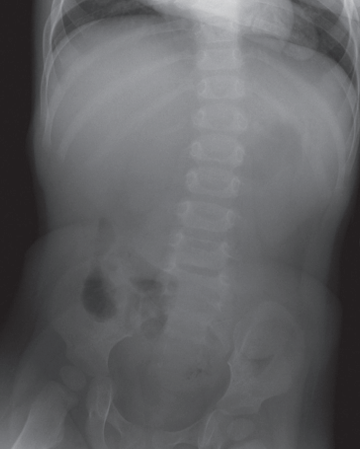

Fig. 56.1A

Esta imagen muestra una masa de tejidos blandos muy sutil que protruye hacia la luz intestinal; dicha anomalía se proyecta sobre el lado izquierdo de la pelvis. El hallazgo resultó corresponder a una intususcepción.